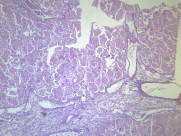

大叶性肺炎(lobarpneumonia)主要是由肺炎链球菌引起,病变累及一个肺段以上肺组织,以肺泡内弥漫性纤维素渗出为主的急性炎症。病变起始于局部肺泡,并迅速蔓延至一个肺段或整个大叶。临床上起病急骤,常以高热、恶寒开始,继而出现胸痛、咳嗽、咳铁锈色痰,呼吸困难,并有肺实变体征及外周血白细胞计数增高等。病程大约一周,体温骤降,症状消失。该病多发生于青壮年男性。疾病常见诱因有受凉、劳累或淋雨等。属于中医“风温”、“肺痈”等范畴。